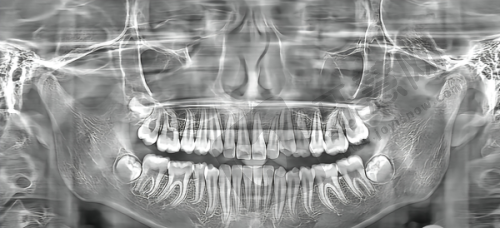

在临床成效方面,韩国uf种植体凭借其开放螺纹和Hsa表面处理技术,能够较好地与牙槽骨结合,在一定程度上确保了种植的稳定性。不过,由于它所属的DIO品牌是二线品牌,在临床数据的积累和大规模的临床验证方面可能相对奥齿泰要少一些。

奥齿泰种植体由于进入市场较早,有大量的临床数据支持。其多孔纳米氧化钛技术和多重微螺纹设计使得种植体的生物活性强、稳定性高,在长期的临床使用中表现出了较高的成功几率和较好的预后成效。特别多患者在使用奥齿泰种植体后,都能获得良好的咀嚼功能和美观成效。

综合来看,虽然目前临床上没有正确的数据显示哪个种植体寿命更长,但从临床经验和数据积累来看,奥齿泰种植体在临床成效方面可能更有优势。不过,具体的临床成效还会受到患者自身口腔状况、医生的种植技术等多种因素的影响。